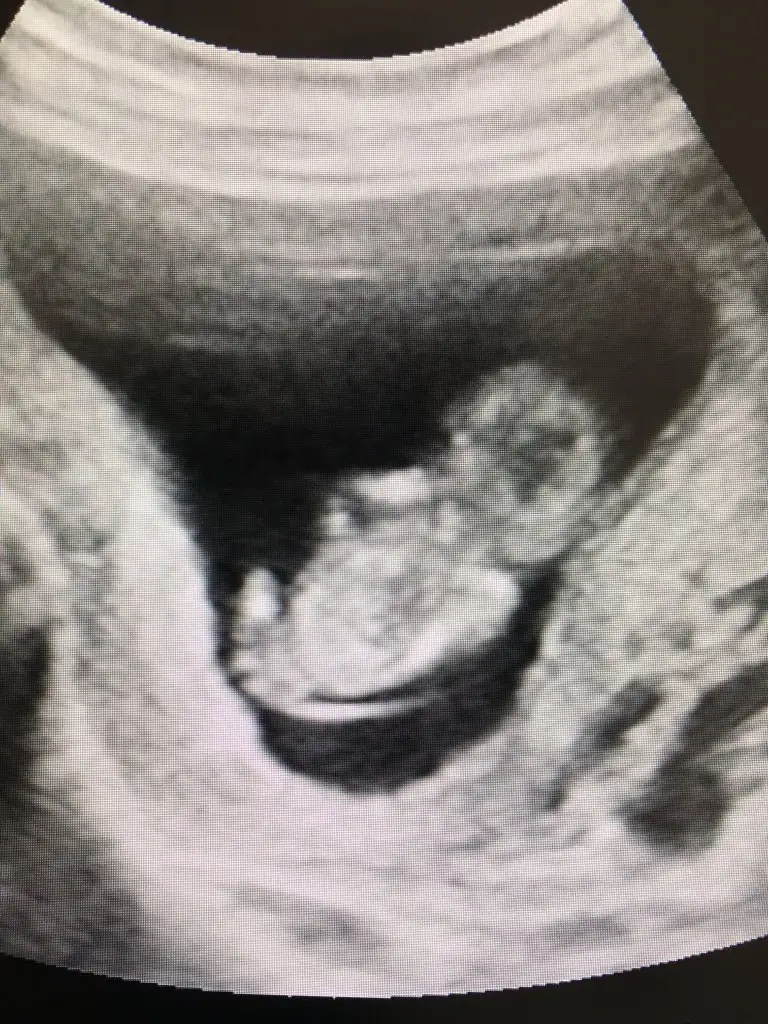

Emin olamadımBenimkinide yorumlar mısın Eki Görüntüle 2896165

bu yorum bana mı acaba :)Emin olamadım şimdilik erkek yönünde ama en iyi 11 12 13 haftalar olmalı